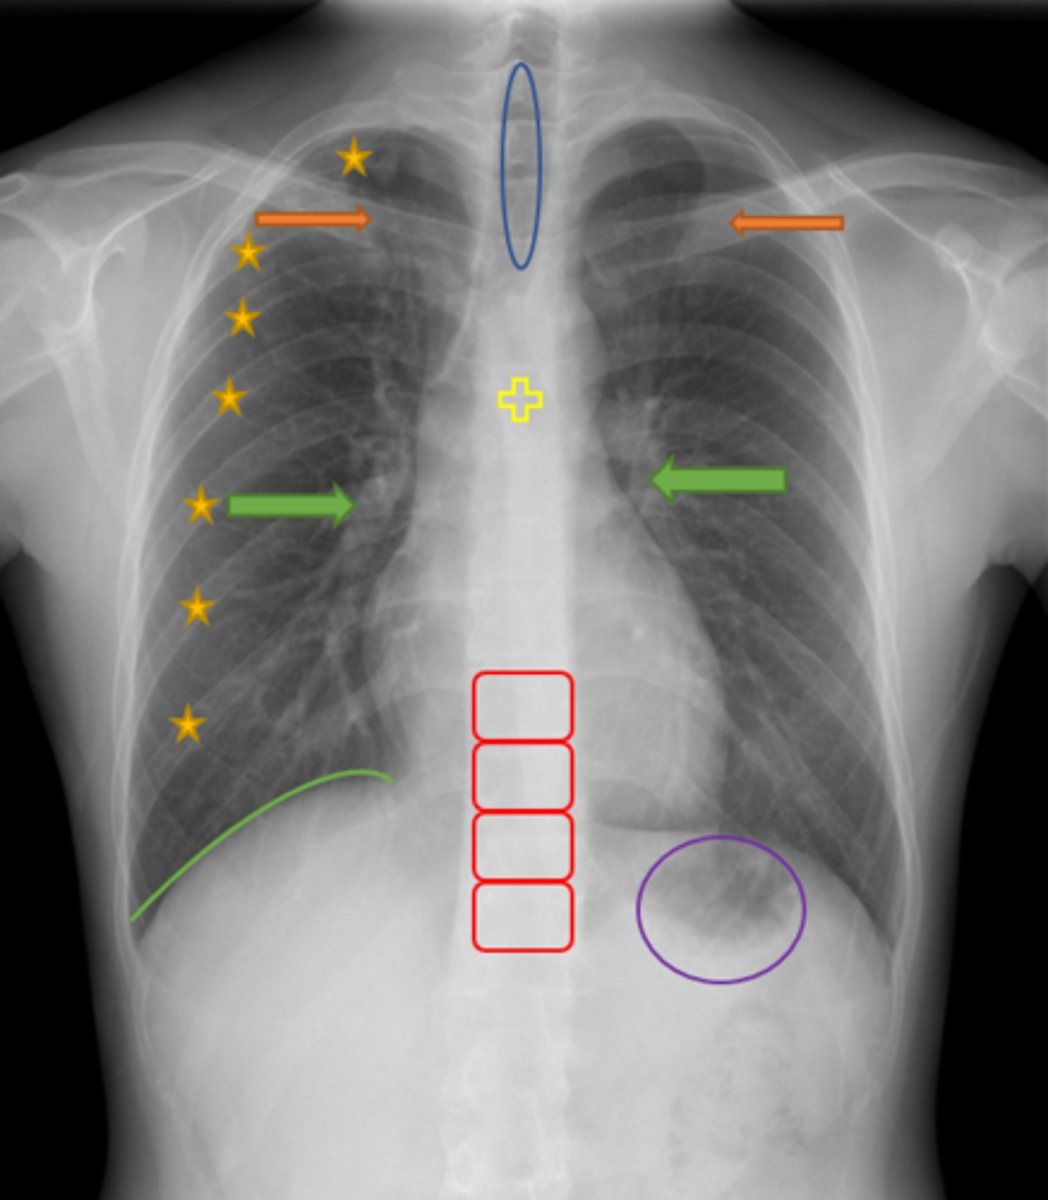

Trachea

Blue Oval

Pulmonary arteries

Green Arrows

Vertebrae/spine

Red Blocks

Clavicle

Orange Arrows

Ribs

Yellow Stars

Diaphragm

Green Line

Gastric bubble/stomach

Purple Circle

Carina

Yellow Cross